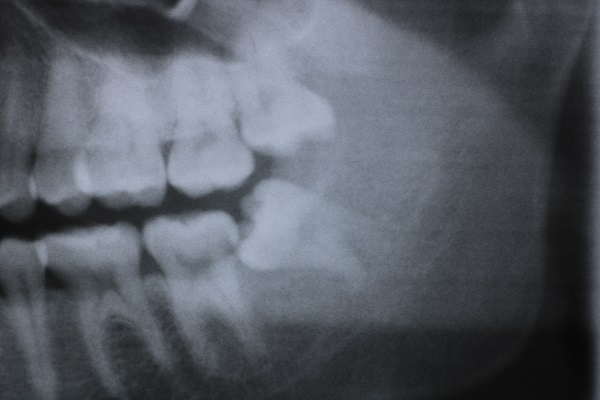

7親知らず

Case8